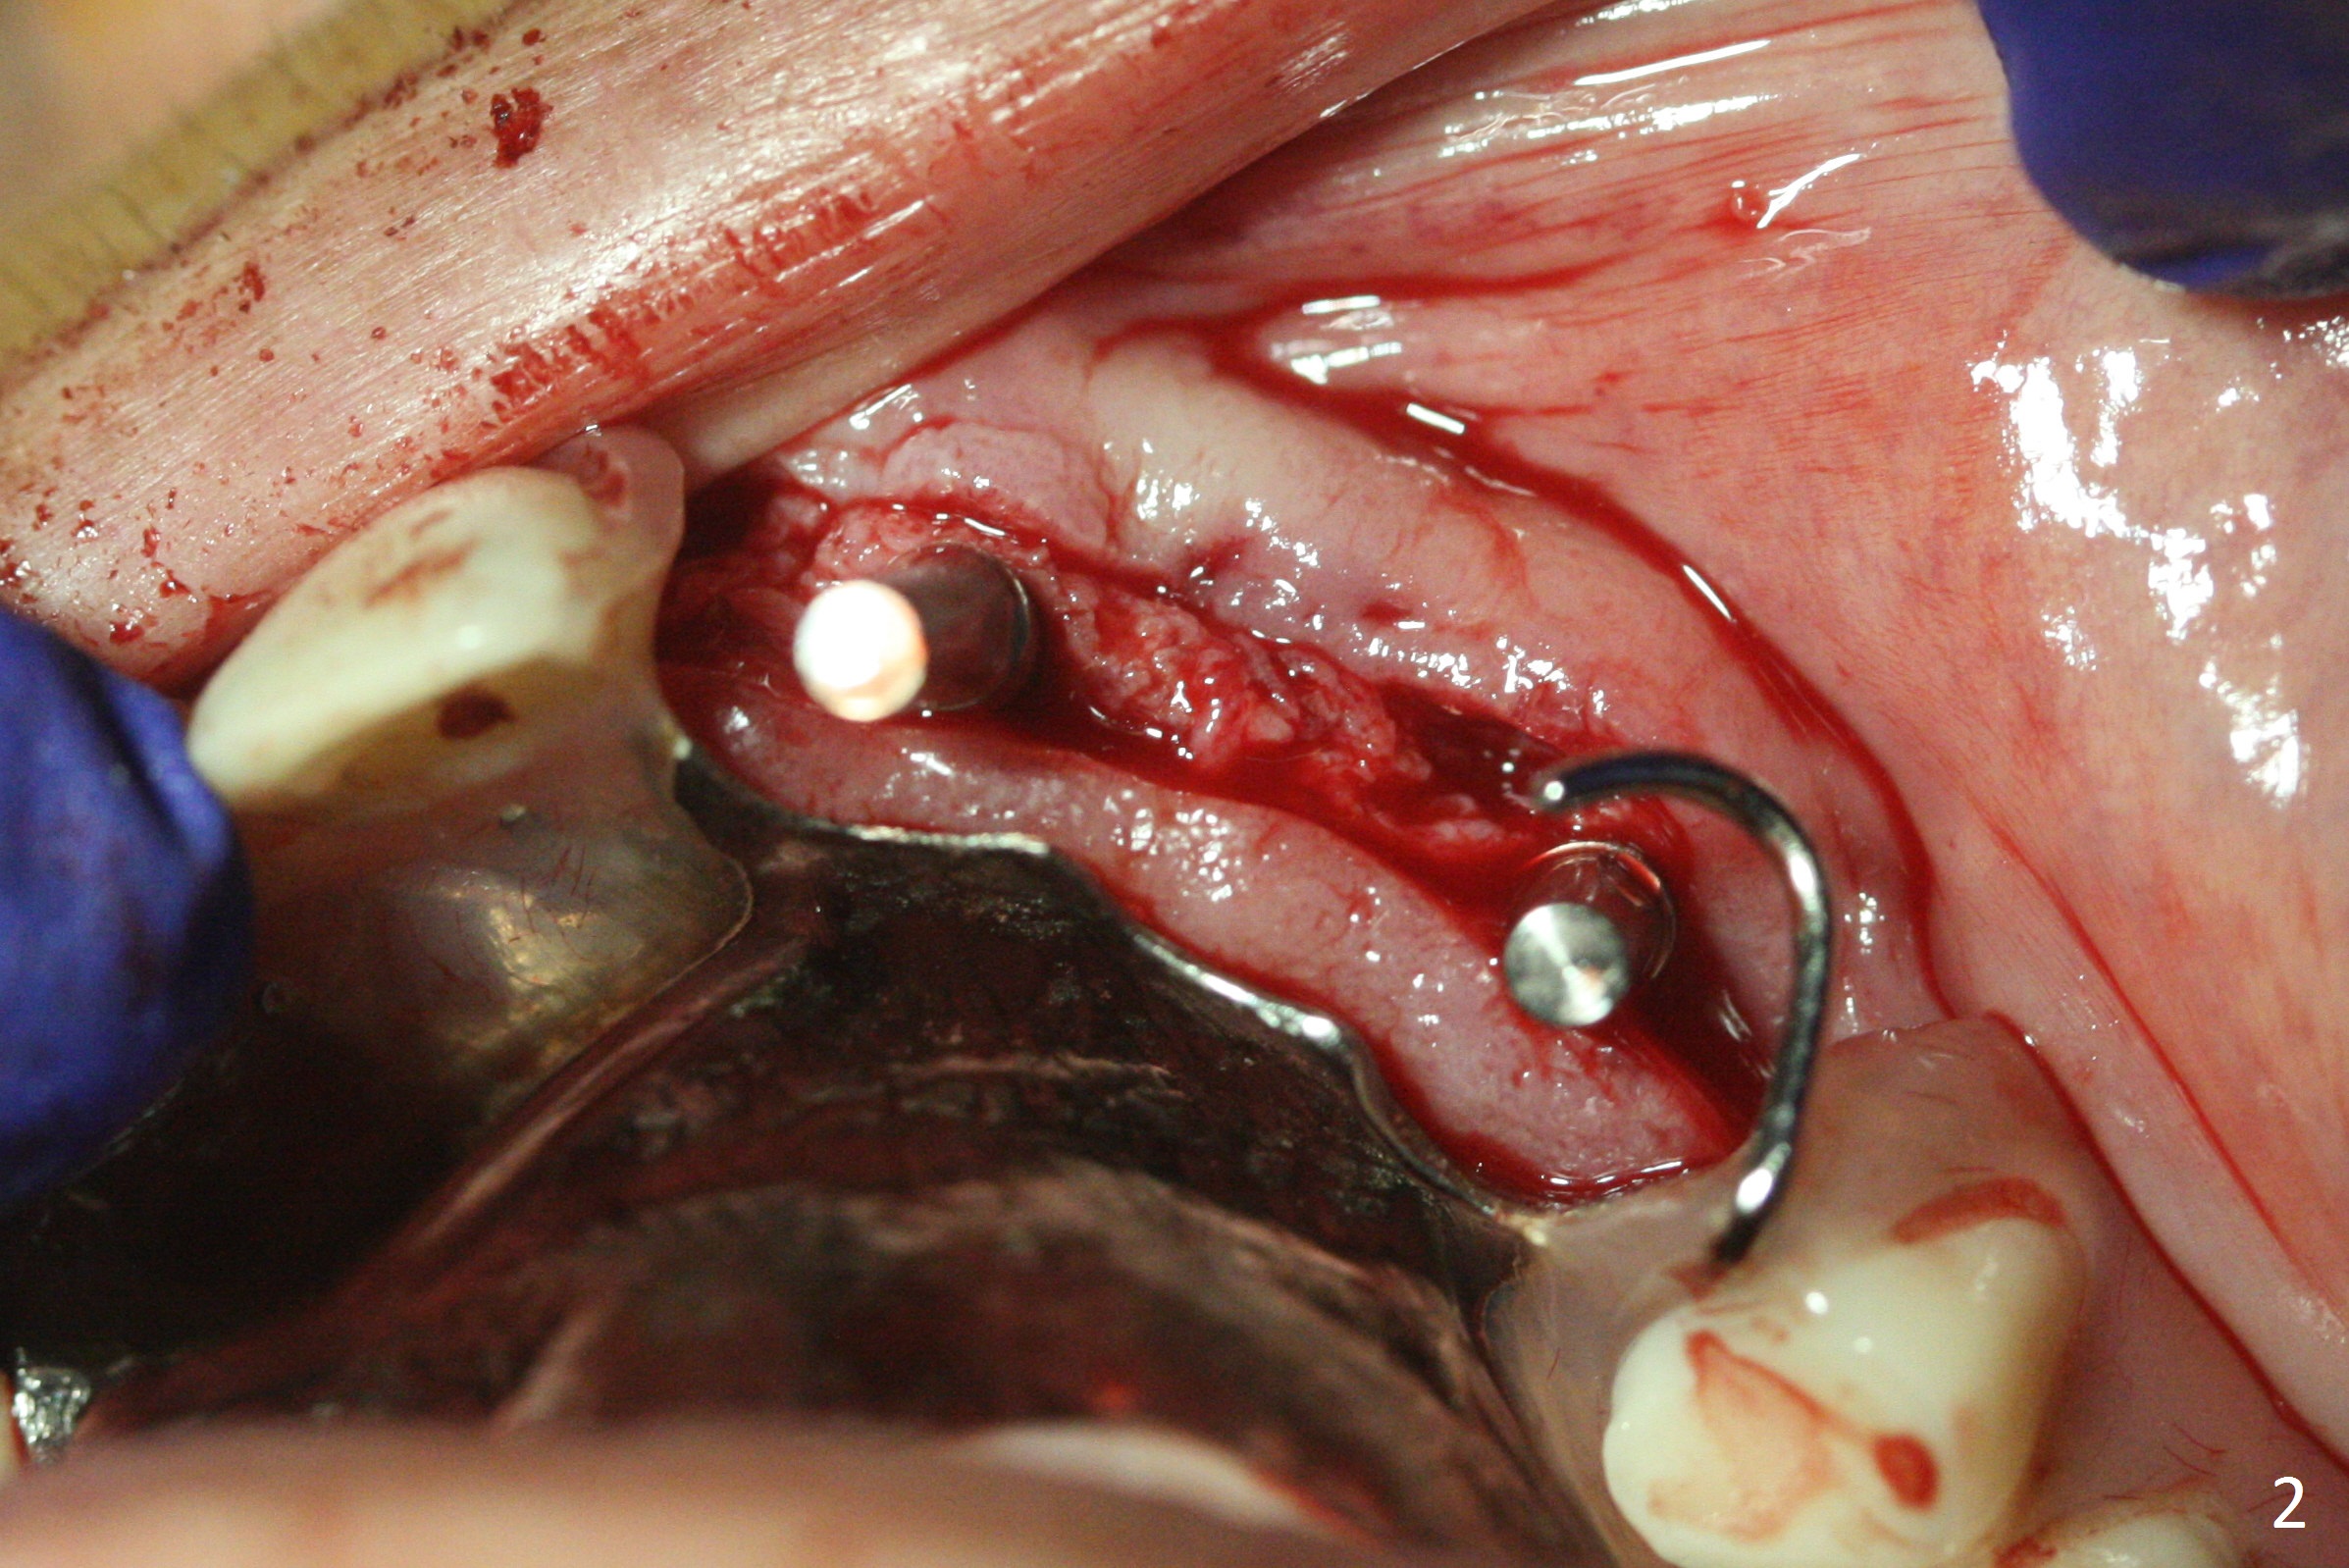

Incision reveals that the ridge at #9 and 11 is narrower than expected. A 3x14 mm 15º 1 piece implant is placed at the site of #9, while a 3x17 mm straight 1-piece one is placed at #11 (Fig.1,4). Insertion torques at #9 and 11 are 20 and 30 Ncm, respectively. The relatively low insertion torque is partially due to osteoporosis. The 65-year-old lady also has dry mouth. Osteotomy should be underprep. The position and trajectory of the implants are dictated by the partial denture (Fig.2). After minor abutment adjustment (Fig.3), an immediate provisional bridge is fabricated. There is no interference when the partial is removed and inserted. After bone graft (Fig.4 ^) and Osteogen Membrane, the ridge (Fig.3) is wider than before. The patient returns for reline 2 months postop (Fig.5-7). In spite of insufficient oral hygiene, the gingiva remains healthy around the implants. To form distinct papillae, acrylic should be added to (Fig.8 yellow line) and removed from (hushed area) the individual provisional crowns. One month after provisional modification (Fig.10, as compared to Fig.5), the pontic recipient site is concave (Fig.11) and becomes less concave after cord packing and abutment trimming. When the provisional bridge is reseated after impression (Fig.12), the pontic recipient site must be blanched again. Please trim the pontic recipient site of the model ~ .5 mm to enhance cosmetics. Water Pik has been used since surgery, but it may be related to loss of bone graft 3.5 months postop (Fig.9 *). One month post cementation, the patient has complained of pain when water pik is irrigating the gingiva palatal to the FPD, apparently in association with denture-related Candidiasis. Two weeks of use of Mycostatin Oral Suspension, peri-implantitis or peri-implant mucositis-like signs and symptoms disappear (Fig.13). CBCT taken 6 months postop confirms that the implants appear to be have been placed in the bone (14,15). The FPD appears to be loose 2.5 years post cementation.